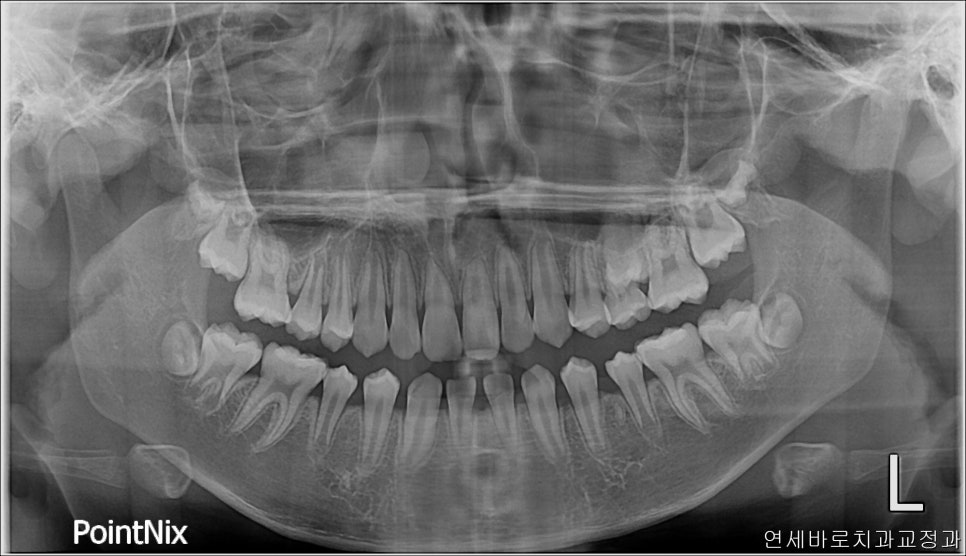

이 친구는 약간의 돌출도 보이고 있었기 때문에 위쪽 치아를 두개 발치했었습니다.

약2년의 치료기간이 걸렸으며 올해 초에 정기검진을 왔습니다

치료가 끝난지 약 3년정도 지난 모습인데 긴밀한 교합으로 인해 치료결과가 잘 유지되고 있는 것 같습니다.

오랜 시간이 지난 뒤 엑스레이에서도 부작용이 관찰되지 않고 잘 유지되고 있네요